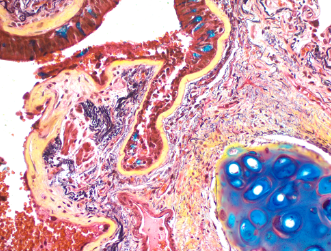

Feulgen Stain Kit ab245878 is a histochemical reagent kit for quantifying the nuclear DNA content in cells.

Feulgen Stain Kit ab245878 is a histochemical reagent kit for quantifying the nuclear DNA content in cells. The kit can be used on a variety of specimen types from cytocentrifuge preparations to formalin fixed paraffin embedded tissue sections. A unique formulation eliminates dye precipitation and results in a cleaner stain than conventional Feulgen reagent-based kits. This stain kit is optimized for DNA Ploidy specimens that will be stained then scanned and viewed on image analysis systems. This kit is designed for cytological specimens prepared from cytospins, smears, cell imprints, disaggregated tissue, or whole tissue.The amount of stain color developed is directly proportional to the amount of DNA present in the stained cells.**Staining Interpretation:**Nuclei: Blue.Nucleoli: Light spaces within the nuclei with dark edges.Cytoplasm: Transparent with no staining.**Note:** Strongly acidic mucous may occasionally stain blue/green.**Control Tissue:**Cytological specimens prepared from whole tissue, disaggregated tissue, cell imprints, smears, or cytospins.Avoid Bouin’s stain as it hydrolyses DNA.**Other products for staining tissue sections**Find more kits and reagents in the , or products for antigen retrieval, blocking, signal amplification, visualization, counterstaining, and mounting in the .